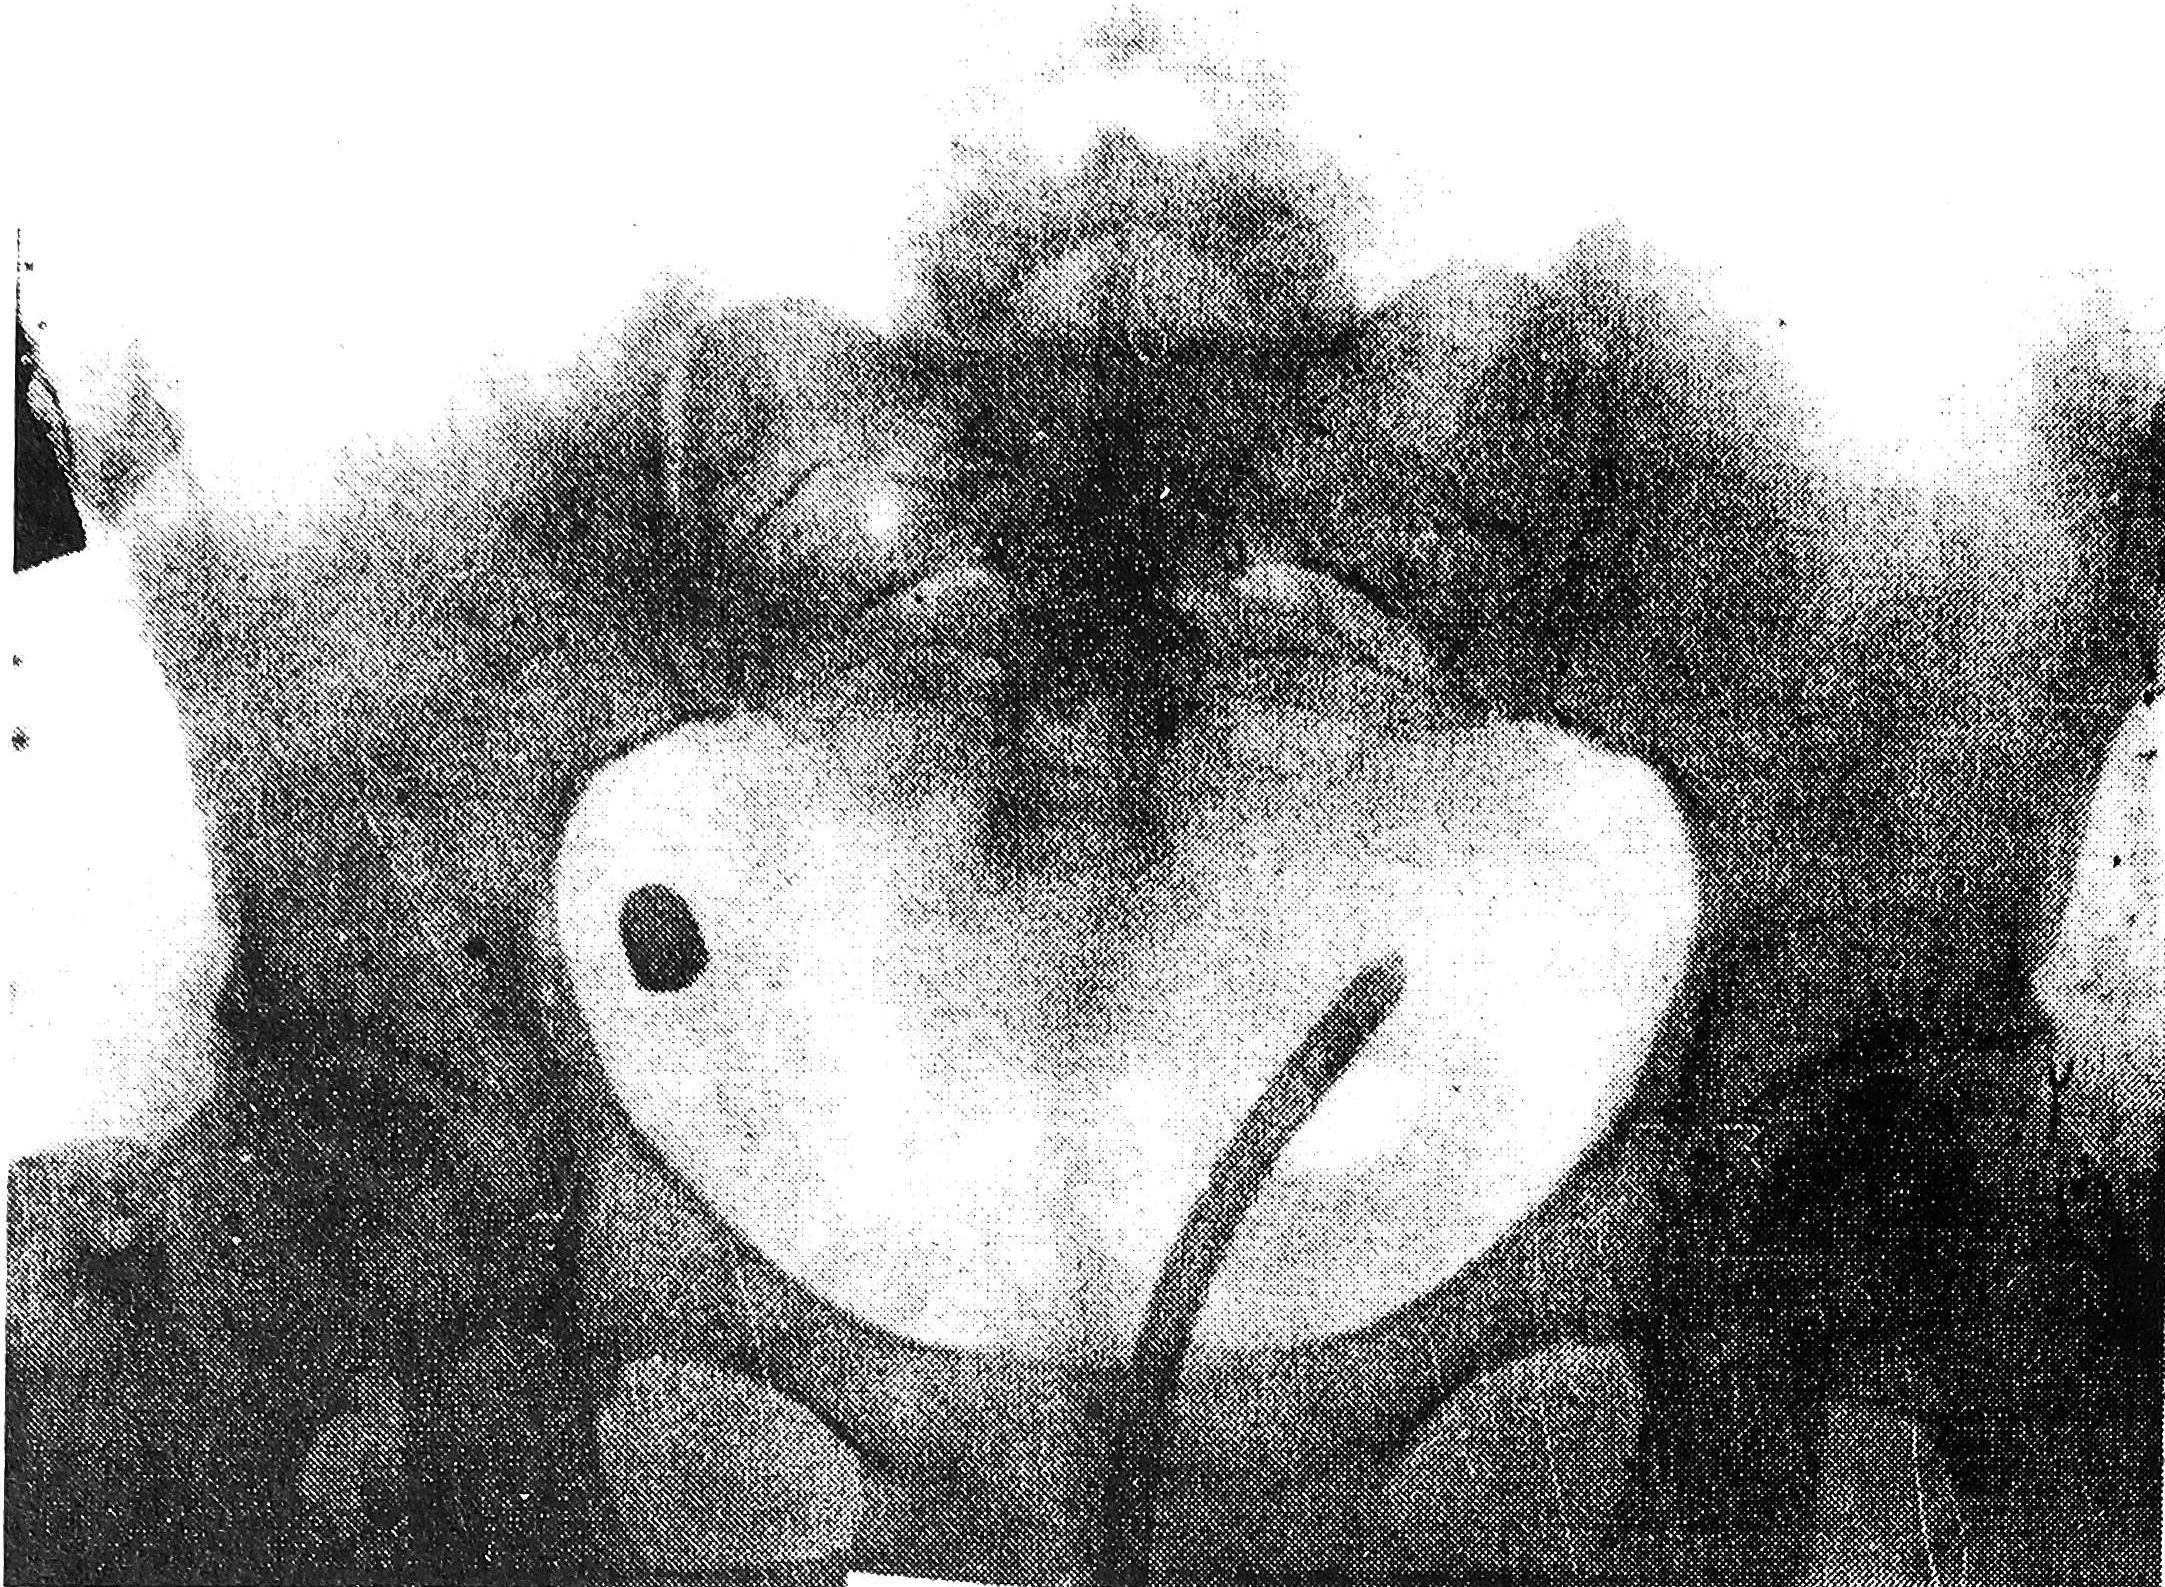

Рис. 1. Рентгенограмма. Справа отчетливо видно инородное металлическое тело - пуля.

Рис. 2. Рентгенограмма (боковая проекция).

Рис. 3. Рентгенограмма (пояснение - в тексте).